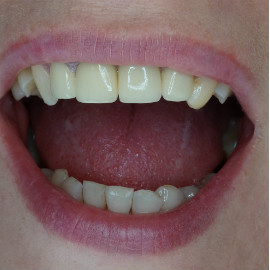

Po utracie zęba w przednim odcinku łuku zębowego należy zwrócić wzmożoną uwagę na aspekt estetyczny. Naczelnym przesłaniem odbudowy brakujących tkanek (anatomiczno-funkcjonalny kompleks tkanek: kość wyrostka zębodołowego + dziąsło + zęby) jest uzyskanie takiego wyniku, który jest najbliżej ideału, czyli takiej sytuacji jak gdyby nic się nie stało i w ogóle nie doszło do utraty zęba i tkanek około zębowych. Kluczem do sukcesu jest odtworzenie poprawnych stosunków anatomicznych: kość - dziąsło - ząb.

Korona protetyczna na implancie, funkcjonująca od roku 2003. Zdarzył się wypadek motocyklowy. Widzimy klucz do osiągnięcia sukcesu: mikrochirurgia i poprawna anatomiczna odbudowa tkanek. Tego nie zastąpi nawet najdroższy implant!

Pokazano etapową odbudowę brakujących tkanek, wraz z odbudową objętości i kształtu dziąsła.

Odbudowa tkanek i zębów przy wysokiej linii uśmiechu. Zadowalający wynik estetyczny.

Odbudowa brakującej kości, odbudowa anatomicznych stosunków dziąsła i korona całoceramiczna osadzona na łączniku cyrkonowym.